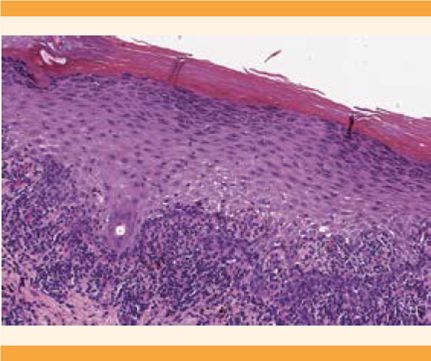

El seguimiento en la consulta de Ginecología fue a las 6 semanas, para valorar la evolución de las lesiones vulvares; se evidenció la desaparición completa de las lesiones de la mucosa vulvar, sin cambios cicatriciales, hallazgos sugerentes del diagnóstico de liquen plano vulvar, subtipo pápulo-escamoso. El reporte anatomopatológico de la biopsia fue de: hiperqueratosis e hiperplasia epidérmica, con crestas en dientes de sierra, e infiltrado linfocitario en banda, liquenoide, con queratinocitos apoptósicos asociados. El diagnóstico definitivo fue: liquen plano. Figuras 4 y 5

Figura 5 Hiperqueratosis e hiperplasia epidérmica, con crestas en dientes de sierra e infiltrado linfocitario en banda (hematoxilina-eosina 10xT).